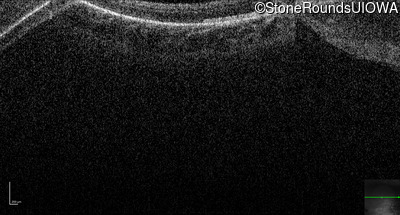

Optical Coherence Tomography - Right - 20/2000

Exemplar / OCT Stack